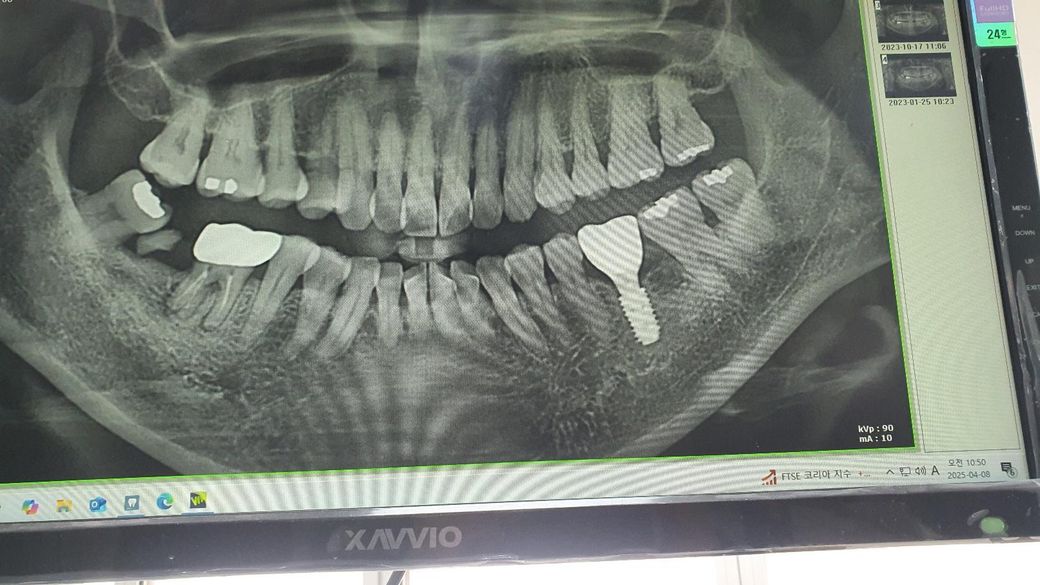

임플란트 식립후 염증 부작용 맞나요?

임플란트를 식립한지 1년 넘었는데요.

음식물이 자꾸 끼고 부작용으로 염증이 생겨서

자꾸 아픕니다.

그래서 크라운을 4번이나 탈부착 했는데도 염증이 계속 생깁니다.

잇몸 빈공간이 문제 인것 같은데 , 픽스처를 빼고 다시 심어야 되나요? 아님 지대주가 문제인가요?

맞춤형지대주라고 하긴 했는데 기성지대주인지 확실히 모르구요.